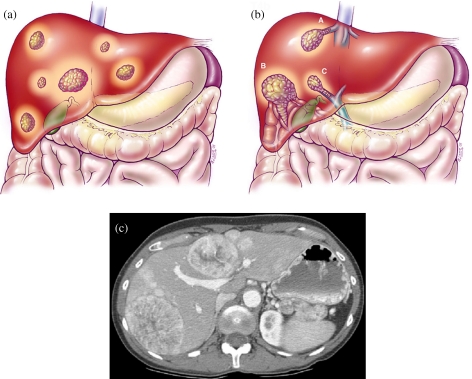

Để chẩn đoán u gan đa ổ, bác sĩ thường bắt đầu bằng các xét nghiệm máu, đặc biệt là với nồng độ AFP, vì khi nồng độ này cao có thể gợi ý tới ung thư gan. Siêu âm ổ bụng là kỹ thuật cận lâm sàng đầu tiên giúp khảo sát tình trạng gan, tiếp theo có thể là chụp cắt lớp vi tính (CT) hoặc chụp cộng hưởng từ (MRI) để xác định rõ hơn về các khối u.

Ngoài việc xác định tính chất lành tính hay ác tính của khối u, chẩn đoán cũng cần đánh giá chức năng gan thông qua các xét nghiệm liên quan. Việc hiểu rõ về tình trạng gan sẽ giúp bác sĩ quyết định phương pháp điều trị hiệu quả nhất, có thể bao gồm phẫu thuật, hóa trị hay phương pháp đốt khối u bằng sóng cao tần.